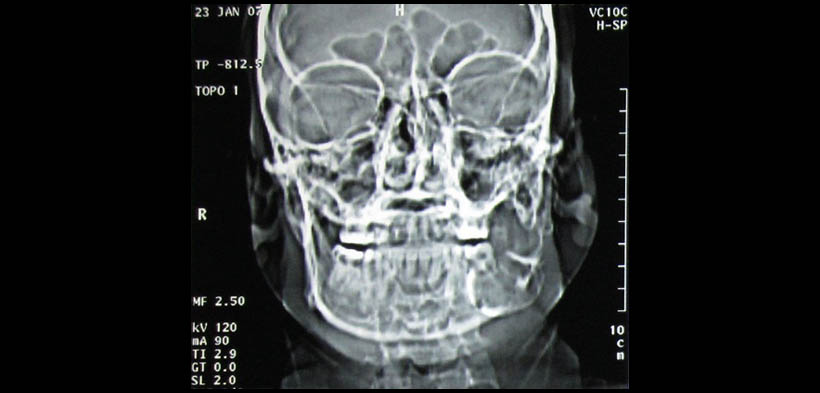

Los hallazgos inusuales de la TC pueden evidenciarse en aquellas lesiones de gran crecimiento y larga data que pueden causar desfiguración de las estructuras circundantes debido a la presión, sin la necesidad de invadir dichas estructuras. Arora, et al realizaron un reporte de caso de un ameloblastoma pleximorme localizada en el cuerpo ángulo y rama mandibular izquierdo, y cuyo crecimiento produjo la deformación de la hemimaxila de dicho lado, considerándose a este hallazgo como algo inusual (fig.1-4)(1).

Fig. 2. Tomografía computarizada (TAC) , vista coronal, se muestra la expansión de la tabla ósea vestibular.